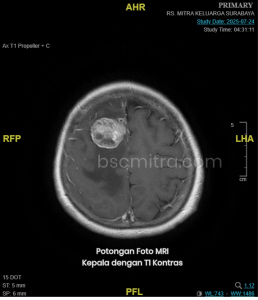

Operasi Tumor Otak: Prosedur, Risiko, dan Harapan Kesembuhan

Operasi tumor otak adalah salah satu tindakan medis yang dilakukan untuk mengangkat atau mengecilkan ukuran tumor yang berada di dalam otak. Operasi tumor menjadi pilihan utama ketika tumor menyebabkan gangguan fungsi otak, tekanan di dalam otak, atau berisiko mengancam jiwa. Banyak pasien merasa cemas ketika mendengar kata “operasi tumor otak”, namun teknologi bedah saraf saat ini jauh lebih aman dan presisi.